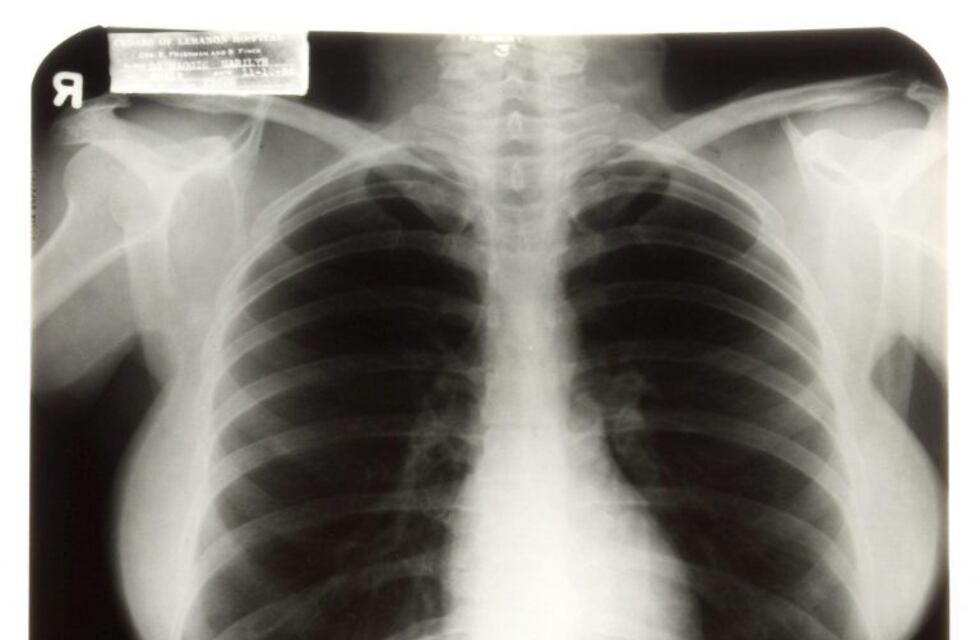

Dos alumnos de la carrera de Ingeniería de Sistemas de la Universidad Católica de Córdoba, inventaron una forma de detectar si una persona está infectada con coronavirus a partir de una radiografía de tórax.

Se trata de Tomás Giraudo y Octavio Di Marco, quienes elaboraron un modelo basado en ciencia de datos para la predicción de infección pulmonar por Covid-19, mediante el análisis de estas imágenes.